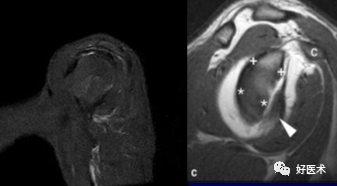

3)完全性撕裂

原发征象:肌腱局部缺如,连续性液体信号横贯肌腱的全层,这使得盂肱关节和肩峰下滑囊相通。

继发征象:

①肩峰下滑膜囊积液,积液在T1WI /PDWI上呈中等信号,T2WI+FS上呈高信号;

②冈上肌肌肉、肌腱结合处回缩(正常位置在肱骨头上方);

③滑囊旁脂肪垫的渗出丢失。

MR 关节造影:局限性或弥漫性充满造影剂的裂隙贯穿肌腱全层,肌腱失去其连续性。

冈上肌腱不完全撕裂

冈上肌腱不完全撕裂伴肩峰下囊积液